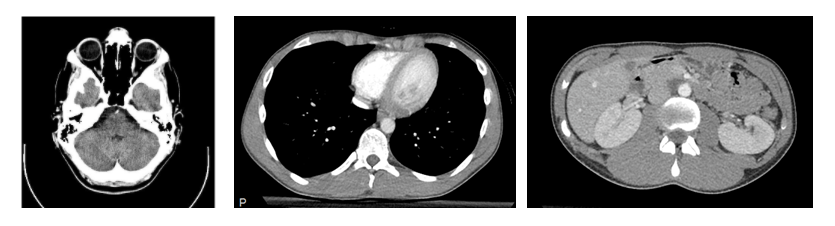

Some examples of CTs of different anatomic regions are shown here:

Examples of CT scans of different anatomical regions. From left to right, the images show the head, the chest, and the abdomen. The images are from Wikipedia (Creative Common licenses): head CT, chest/abdomen CT.